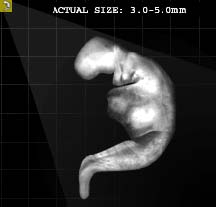

A Korán Allah szava, amelyet Mohammed Prófétának (Allah áldása és békéje Reá) küldött le a Földre Gábriel angyal segítségével. Mohammed Próféta (Allah áldása és békéje Reá) feladata volt, hogy átadja az Iszlám üzenetét az emberiségnek. A Korán így Allah egyik csodája, olvasása közelebb viszi a hívőket Urukhoz, s közbenjáró is lesz a hívőkért az Ítélet napján. A Korán csodás a történetei terén, minden korábbi írásnál sokkal teljesebb, pontosabb leírást ad a Paradicsomról és a Pokolról is, az egész Túlvilágról, a Feltámadás Napjáról, arról, hogy mi történik a halál után. Csodás a törvénykezés terén, az élet valamennyi területére nézve gyakorlati útmutatót is tartalmaz. Egyedülállóságát bizonyítja, hogy amikor még a kalifátus létezett, és egy állam vezetése is az Iszlám törvénykezésnek (Sariának) megfelőlen valósult meg, az az Iszlám fénykora volt, s az embereknek a legjobbat jelentette. Sajnos mára már egyetlen ország kormányzása sem e törvénykezés, azaz az isteni törvények alapján történik. A Korán csodás a tudományok terén is, számos olyan tényt tartalmaz, amelyet az egyes tudományokban csak jóval a kinyilatkoztatása után fedeztek fel. Például a fejlődéstanra vonatkozólag részletesen leírja a magzatfejlődést. Olyan dolgokat is megtalálhatunk benne, amelyeket később a csillagászatban, természettudományok terén fedeztek fel. E felfedezések összhangban vannak a Koránban leírtakkal. (Komáromi, 2005) Jónéhány tudós ezért vált muszlimmá, mert megvilágosodott előttük a Korán csodája a tudomány terén, s minden más tekintetben is.

9 Az ájának ez a része azt jelenti, hogy ha egy muszlim embernek a családtagját megölték és Iszlám bíróság előtt, bírósági per lefolytatása után a gyilkos vétkesnek bizonyult, akkor a legközelebbi hozzátartozó a gyilkos halálbüntetését kérheti. Ettől a jogától azonban el is állhat. Ez kizárólag Iszlám államban történhet meg és csak teljes bizonyosságot nyert gyilkosság esetén. Allah azonban azt is mondja a Koránban, hogy jobb ha a hozzátartozó illetve a család megbocsát inkább a gyilkosnak és nem kérik a halálbüntetését. Ez a törvény leginkább elrettentésül szolgál, azért hogy minden hívő illetve nem hívő is tudja, hogy az emberölésnek mekkora súlya van és meg se forduljon a fejében egy ilyen tettet elkövetni. Illetve, hogy annak, akinek mégis ilyen szándéka van, azt visszatartsa ez a törvény ettől a tettől. Egy hívő embernek azonban nyilvánvalóan nem lehet soha ilyen szándéka, de még gondolata sem.